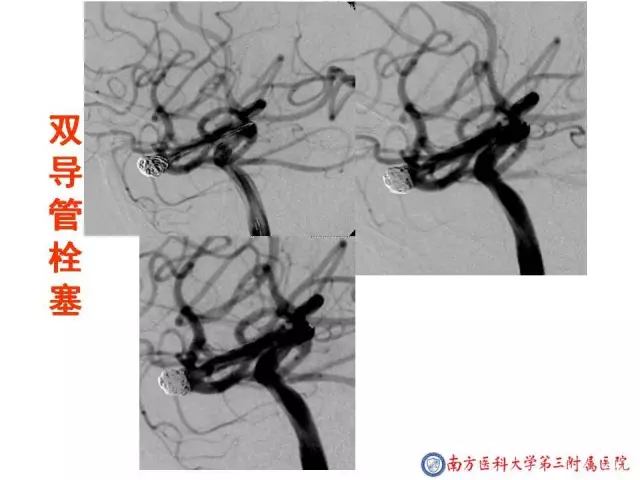

今天为大家分享的是“强生医疗CNV-神经介入专栏”第二十五期,由南方医科大学第三附属医院神经外科主任黄理金教授带来的“Enterprise支架辅助栓塞动脉瘤的优势”精彩讲课视频及PPT,欢迎观看。文章仅代表作者个人观点,如有不同见解,欢迎同道斧正!